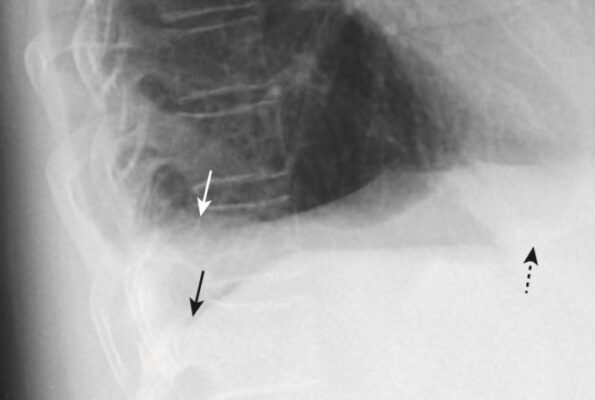

U giả phổi ở rãnh liên thuỳ (Fissural Pseudotumors)

- Các khối u giả là những tụ dịch màng phổi có bờ sắc rõ nằm hoặc giữa các lớp một rãnh liên thuỳ phổi hoặc ở vị trí dưới màng màng phổi ngay dưới rãnh. Đó là dịch thấm hầu như luôn xảy ra ở bệnh nhân suy tim sung huyết.

- Các dấu hiệu hình ảnh của một khối u giả là đặc trưng, vì vậy không nên nhầm chúng với một khối u thực sự.

- Chúng có hình thấu kính, thường xuất hiện nhất ở rãnh liên thuỳ bé (75%) và thường có đầu nhọn ở mỗi bên, nơi chúng lách vào rãnh liên thuỳ, giống như hình dạng của quả chanh. Chúng không có xu hướng di chuyển tự do khi thay đổi tư thế bệnh nhân.

- Chúng biến mất khi bệnh lý nền (thường là suy tim sung huyết) được điều trị, nhưng có xu hướng tái phát ở cùng một vị trí mỗi khi suy tim tái phát (Hình 14).